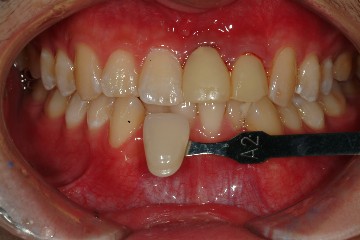

由於是前牙,本院採用Cynovad數位比色機比色(圖十六,並以高階數位單眼相機記錄牙齒的表面紋路及局部色澤(染色、斑點等)(圖十七),因此技師即使未親臨現埸,仍可得到最精準的比色資料。

圖十七 |